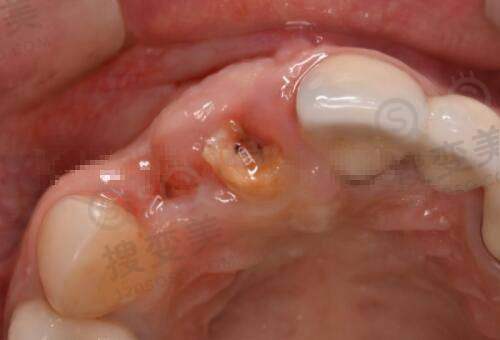

张红歌医生擅长的项目十分广泛。在基础修复类方面,她擅长阴道紧缩术,该手术含生物束带/激光/手术三种方式,会按松弛程度分级收费;小阴唇矫正术,能矫正肥大、不对称等问题,采用显微缝合技术;处女膜修复术,精细分层缝合,术后无痕率≥95%。这些手术都展现了她高超的技艺和精细的操作。

功能治疗类项目中,她针对尿失禁、脏器脱垂等问题,擅长盆底肌修复,含电刺激 + 生物反馈治疗;对于陈旧性产伤修复,她的会阴裂伤修复手术含肌肉重建,能够有效解决患者的困扰。在美学塑形类方面,大阴唇脂肪填充可以用自体脂肪移植丰润外阴;私密漂红(激光)能改善色素沉着,单次维持2 - 3年;阴蒂整形术则包括包皮修整 + 敏感点重塑。